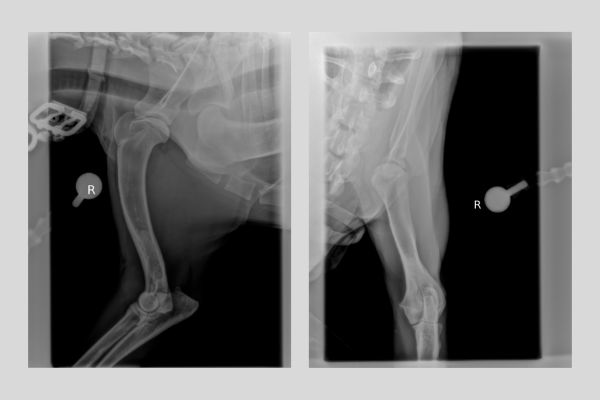

Se realizan radiografías ortogonales del húmero dado que nos pueden orientar en nuestros diagnósticos diferenciales.

En ellas se detecta un aumento de opacidad del canal medular en el tercio distal del húmero derecho.

Diagnóstico

Con las imágenes radiológicas el diagnóstico de panosteitis se confirma.